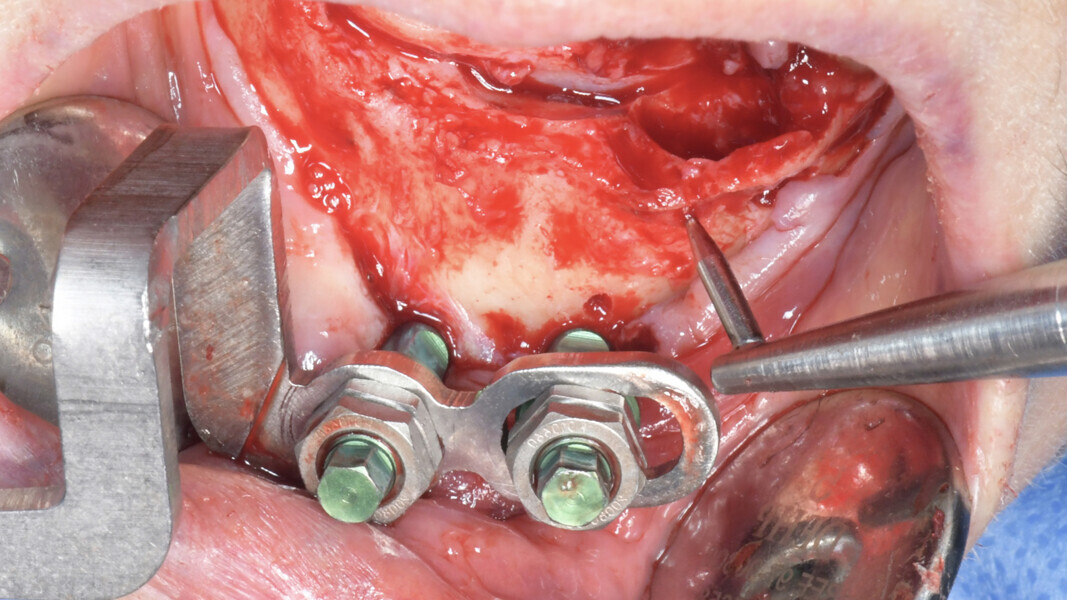

La chirurgie implantaire naviguée peut alors prendre place. Dans ce cadre spécifique, le tracker de repérage du patient est fixé à l’os (vis vertes EDX, X-Nav) et la calibration se fait par le repérage de points osseux par une sonde spécifique (protocole X-Mark ; Fig. 9).

X-Guide est un système de navigation dynamique pour un guidage 3D en temps réel du positionnement des forets sans guide chirurgical. Il est conçu pour améliorer la précision et l’exactitude de la position, de l’angle et de la profondeur de l’implant. Les points de référence sont suivis et affichés en temps réel via deux caméras positionnées entre 60 et 80 cm au-dessus du patient. L’écran guide le chirurgien lors du forage à l’emplacement prévu par le plan d’implant DTX Studio. L’enregistrement virtuel de l’anatomie du patient peut être réalisé avec le protocole X-Mark, ce qui signifie qu’aucun marqueur CBCT n’est requis pour le scan. Trois points sont marqués sur le rendu CBCT dans X-Guide, et les mêmes trois points sont marqués dans la bouche du patient avec une sonde. Pour les cas d’édentements, le tracker de repérage EDX est attaché au patient, dégage la lèvre, et n’interfère pas pendant l’intervention chirurgicale. Il convient à la chirurgie avec ou sans lambeau, et différentes conceptions du tracker de repérage sont disponibles en fonction de la préférence manuelle du chirurgien. Des études ont confirmé une meilleure précision et moins d’écarts par rapport au positionnement prévu de l’implant, par rapport à la chirurgie à main levée.1, 2  Comparé à d’autres systèmes dynamiques testés, X-Guide est trois à quatre fois plus précis.3